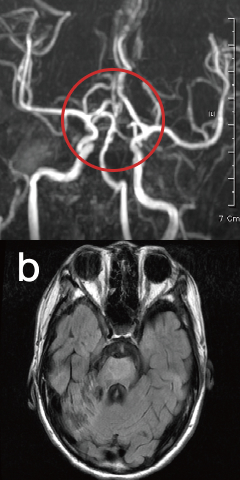

뇌졸중

Stroke-

발병시

-

줄기세포 치료 15일 후

줄기세포 치료 41일 후

끊어진 뇌혈관 주변으로 새로운 혈관이 형성 되었습니다.